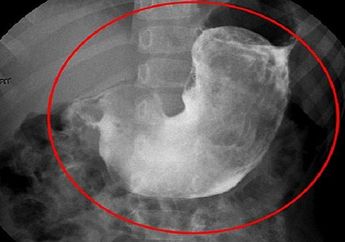

Gadis 9 Tahun Ini Mengeluh Mual, Keluarga Kaget Saat Lihat Gumpalan Berdiameter 18 Sentimeter di Perutnya!

6 Tahun yang lalu - Seorang anak mengeluah mual. Setelah dilakukan CT scan, keluarga terkejut dengan gumpalan berdiameter 18 cm yang ada di perut bocah itu.